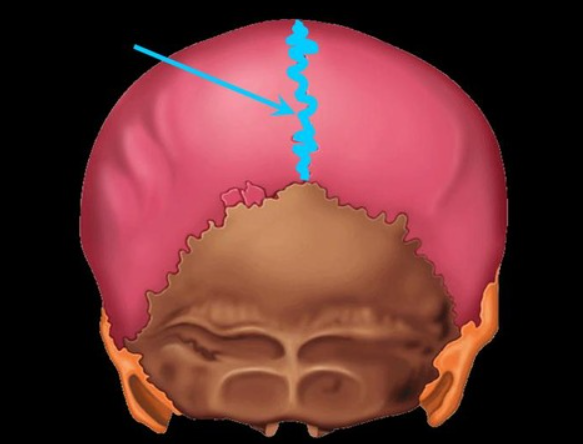

sagittal suture

sits between the right and left parietal bone